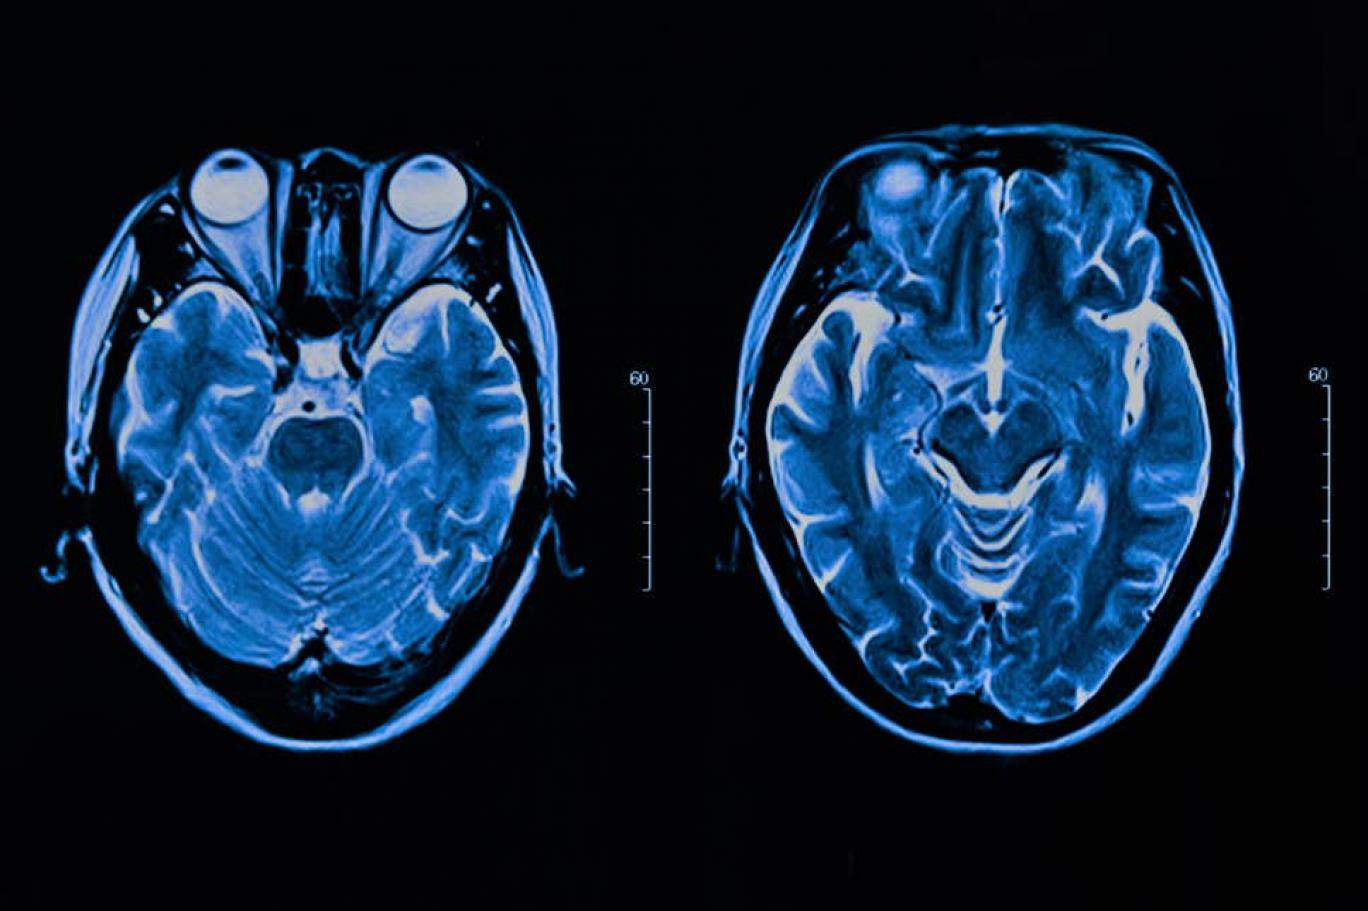

متابعات| استخدم فريق من الباحثين تقنية تعلُّم الذكاء الاصطناعيّ في تحقيق اختراق علميّ لجهة فهم خصائص عدّة للعقل البشريّ لم يكن ثمة مجال لتفسيرها سابقاً.

اكتشف باحثون في "ديب مايند" المملوكة لشركة "غوغل" أنّه يمكن تطبيق تطوّر حديث شهدته علوم الكمبيوتر بشأن ما يُسمى "التعلّم المعزّز"، على كيفية عمل نظام الدوبامين (هرمون المكافأة) في الدماغ. وينطوي البحث الحديث، الذي نُشر في مجلة "نيتشر" العلمية، على فهم أفضل للصحة العقليّة- النفسيّة، علاوة على مشاكل التعلّم والاضطرابات في التحفيز.

ووجد البحث أدلة على أن شيئاً يُشار إليه باسم "تعلُّم معزّز توزيعيّ" يُستخدم في خوارزميات الذكاء الاصطناعيّ يحاكي فعلاً ما يُعرف بـ"نظام المكافأة" الذي ينشط في الدماغ ويؤدي فيه الناقل العصبيّ الدوبامين دوراً مهماً.  وتسمح التقنية الحديثة للدماغ أن يستخدم التوزيع الاحتماليّ للمكافآت المستقبليّة بدلاً من التركيز على الأفعال التي تؤدي إلى مكافآت فوريّة.